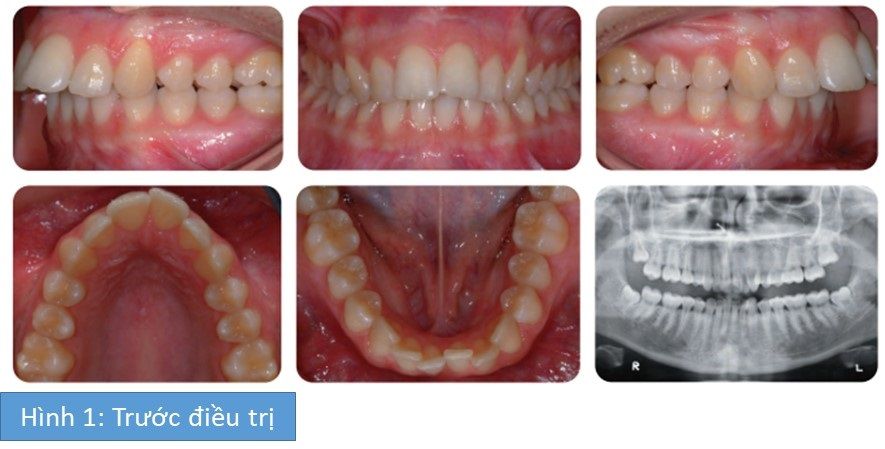

Bệnh nhân nữ 18 tuổi có sai khớp cắn hạng I tiểu loại I trên nền xương hạng II nhẹ với kích thước dọc trung bình, độ cắn chìa tăng đến 10mm và chen chúc nhẹ ở cả 2 cung răng.

Mục tiêu chính của điều trị là giảm độ cắn chìa để ngụy trang sự sai lệch xương hạng II bên dưới. Nhu cầu neo chặn để tạo thuận lợi cho việc giảm cắn chìa là lứn vì tương quan răng hàm lớn trước điều trị là hạng II 1 đơn vị 2 bên và độ cắn chìa tăng nhiều. Do đó, các răng hàm nhỏ thứ nhất hàm trên được nhổ bỏ để kéo lui tối đa nhóm răng trước hàm trên. Các răng cửa hàm dưới dự kiến làm chìa ra ngoài một chút nhằm giảm bớt yêu cầu neo chặn ở cung răng hàm trên. Hơn nữa, khí cụ neo chặn tạm thời (TADs) được đắt phía sau gần răng hàm lớn thứ nhất để ngăn những răng phía sau hàm trên di gần trong khi kéo lui các răng cửa hàm trên. Do đó, duy trì tương quan răng hàm hạng II và cả tương quan răng nanh và răng cửa cũng được sửa thành hạng I.